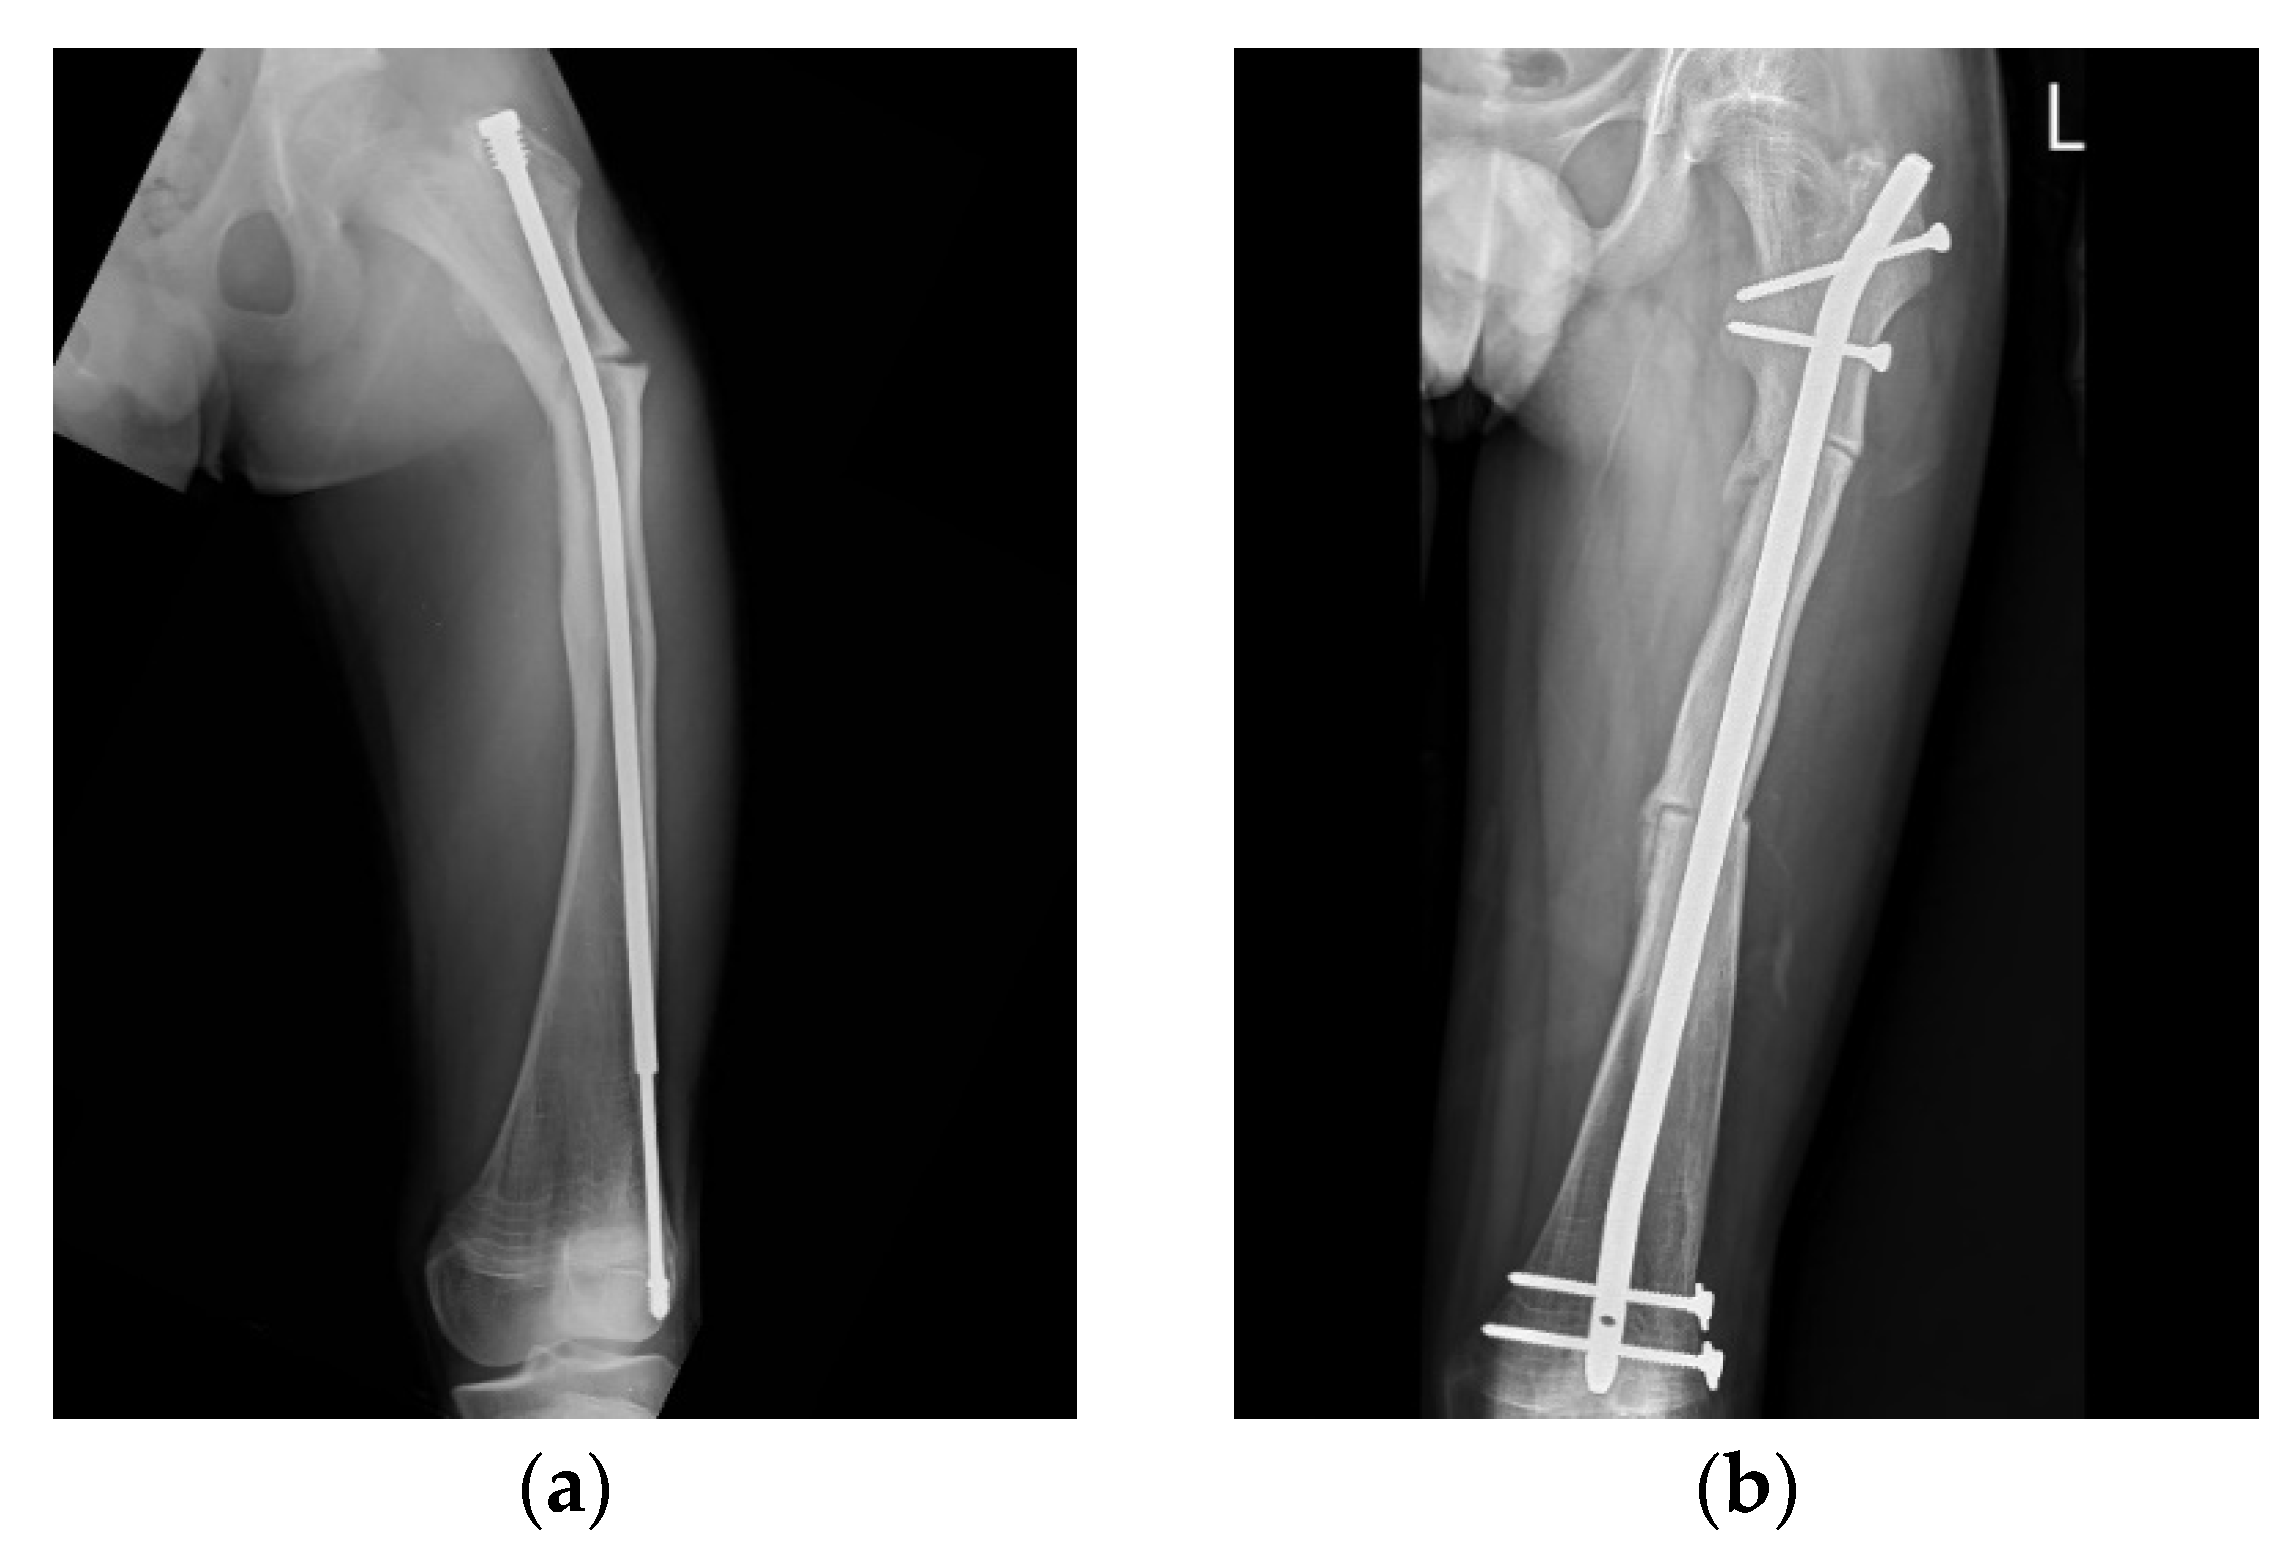

An 11-year-old boy with type IV OI (Figure 4) underwent revision surgery with an FD nail due to implant malposition. When the distal tip of a nail is not placed in the center of the joint, the mechanical axis may become deviated, possibly leading to refracture or nail bending (Figure 4a). In this patient, deviated alignment and a bowed femur caused an imbalance in mechanical stress, which led to a proximal femur refracture. Restoration of the alignment and bowing correction to avoid further implant failure were performed with a pediatric nail after physeal closure (Figure 4b).

Figure 4. Anteroposterior (AP) radiograph of the femur of an 11-year-old male post FD nail implantation. (a) The position of the male component was eccentric in the distal epiphysis. Due to an incorrect mechanical axis, subsequent refracture with nail bending was observed 3 years after surgery. (b) Revision surgery of osteoclasis and fixation with an interlocking PediNailTM.